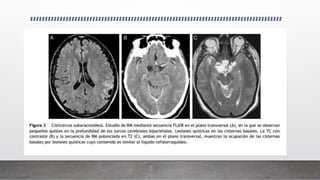

CISTICERSOSIS SUBARACNOIDEA

• La más frecuente.

• El parásito alcanza por vía hematógena las cisternas basales, espacios subaracnoideos y

meninges, desencadenando una intensa reacción inflamatoria perilesional.

• Esta reacción inflamatoria puede afectar las leptomeninges en la base del cráneo y

extenderse hasta el agujero magno, produciendo una leptomeningitis basilar que engloba

nervios y arterias craneales. También se afectan los agujeros de Luschka y Magendie con

hidrocefalia.

• Los cisticercos subaracnoideos pueden ser pequenos ˜ si se localizan en la profundidad de

los surcos corticales o pueden alcanzar tamaños mayores de 5 cm si están en las cisuras de

Silvio o en las cisternas basales.

• Esta localización facilita una degeneración hidrópica por entrada continua de líquido

cefalorraquídeo al interior de la vesícula. En esta situación puede producirse una falta de

formación del pro-escólex o degeneración del escólex, forma denominada racemosa.